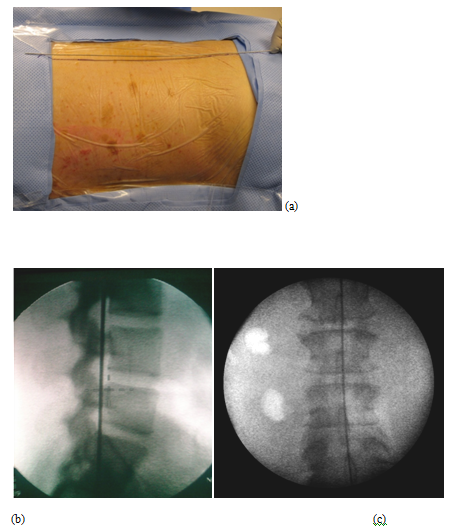

A 63-year-old patient with morbid obesity and insulin dependent diabetes mellitus suffered from spinal canal stenosis and multiple level disc protrusions at L2/3, L3/4, L4/5 and L5/S1. The largest disc was at L5/S1, > 6mm as illustrated below. His weight is 280 lbs and height 5’ 8” (Figure 4–16). The patient complained of back pain and radicular symptoms including the anterior and surface of both thighs and legs, and back of the foot with more severe pain on the right side associated with some neurogenic claudication. Previously the patient refused open surgery with fusion, because of increased risk in morbid obese and diabetic patients and requiring a multi level extensive open spinal fusion. After reviewing his MRI scans, (Figure 4) minimally invasive endoscopic microdecompression surgery was recommended to the patient as a solution for his spinal condition. He agreed to proceed with MISS surgery. It can be very time consuming to reach the foramen in obese patients since the fat distribution gives a false orientation of the actual location of the spine in relation to the skin surface. By using the GPS system to triangulate the 3D orientation of the foramen under fluoroscopy, the height, width and depth of the soft tissue in relation to the foramen was determined the microdecompression was successfully performed. Bilateral L2-L5 endoscopic microdecompressive discectomy (Figure 5–16) was performed in the lateral decubitus position on two sittings of less than 1 hour for each side to avoid a prolonged single procedure. The patient reported marked relief of his back symptoms and lower limb numbness on the next post operative day with a better range of motion and ambulation.

Figure 5 (a) Identifying the foraminal line on patient (b) Fluoroscopic lateral view (c) Fluoroscopic midline or lateral foraminal line (On AP View).